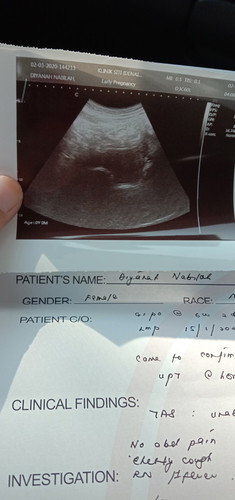

semalam pergi scan doctor kata dah 6 minggu 2 hari tapi stay tak nampak kantung lagi . mungkin kot doctor kata luar rahim

6 minggu 2 hari tak nampak kantung